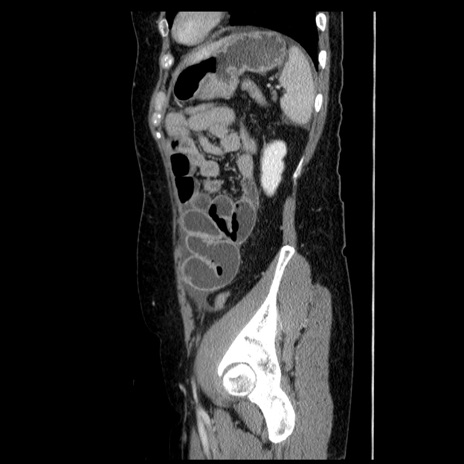

横断像

【症例】50歳代女性

【主訴】下腹部痛

【既往歴】卵巣癌術後(8年前に当院で卵巣摘出)

【身体所見】 意識清明、腹部:平坦、腸蠕動音→、やや硬、下腹部自発痛・圧痛あり、反跳痛あり、筋性防御なし。

【データ】WBC 16000、CRP 0.01